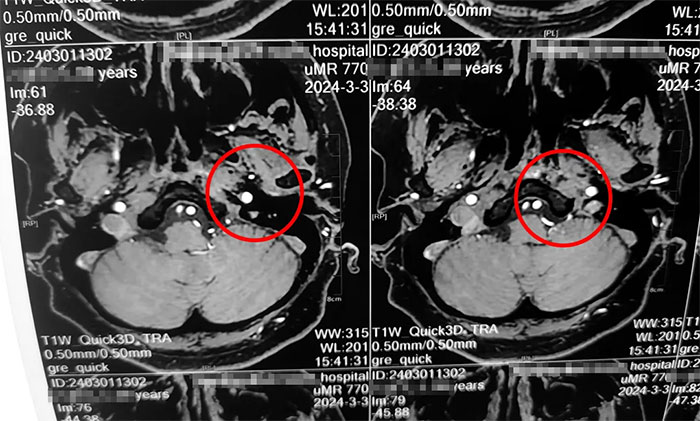

楊忠旭教授詳細了解了劉阿姨的癥狀、病史資料、影像資料等。楊忠旭教授分析指出,傳統(tǒng)的三叉神經(jīng)痛大多發(fā)生于面部,而劉阿姨疼痛的部位為舌頭,和最普遍的三叉神經(jīng)痛位置大相徑庭,但其實支配舌前2/3的感覺的舌神經(jīng),也是自三叉神經(jīng)發(fā)出,所以此處的疼痛完全符合三叉神經(jīng)痛的表現(xiàn)。結(jié)合影像資料,楊忠旭教授指出患者左側(cè)三叉神經(jīng)根部與臨近小血管關(guān)系密切,手術(shù)指征明顯,未見明顯手術(shù)禁忌癥。

▲ 左側(cè)三叉神經(jīng)與臨近小血管關(guān)系密切